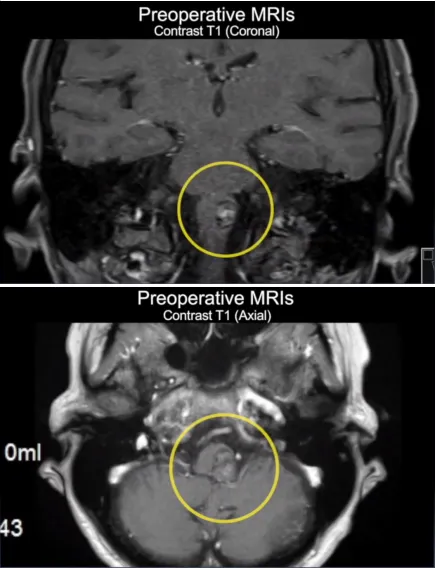

术前影像学检查

术前MRI显示左侧延髓外侧有一个16毫米圆形病变,提示出血性海绵状瘤,病灶的大小比第一次出血后大。